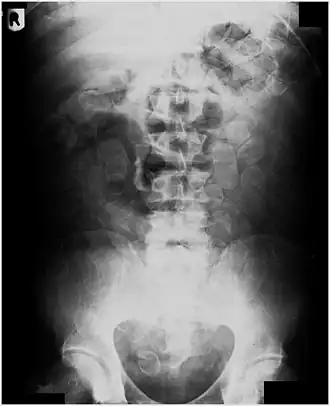

Abdominal X-ray showing swallowed packages of cocaine.

This is often done using a mule's gastrointestinal tract or other body cavities as containers. Swallowing has been used for the transportation of heroin,[1][4][5] cocaine,[6] and MDMA (ecstasy).[7] A swallower typically fills tiny balloons with small quantities of a drug. The balloons may be made with multilayered condoms, fingers of latex gloves,[6] or more sophisticated hollow pellets. One smuggling method involves swallowing the balloons, which are recovered later from the excreted feces. Alternatively, the balloons may be hidden in other natural or artificial body cavities – such as rectum,[6] colostomy,[8] vagina, and mouth[9] – although this method is far more vulnerable to body cavity searches. A drug mule may swallow dozens upon dozens of balloons.[5] The swallower then attempts to cross international borders, excrete the balloons, and sell the drugs.

Routine detection of the smuggled packets is extremely difficult, and many cases come to light because a packet has ruptured or because of intestinal obstruction. Unruptured packets may sometimes be detected by rectal or vaginal examination, but the only reliable way is by X-ray of the abdomen. Hashish appears denser than stool, cocaine is approximately the same density as stool, while heroin looks like air.[11][12]